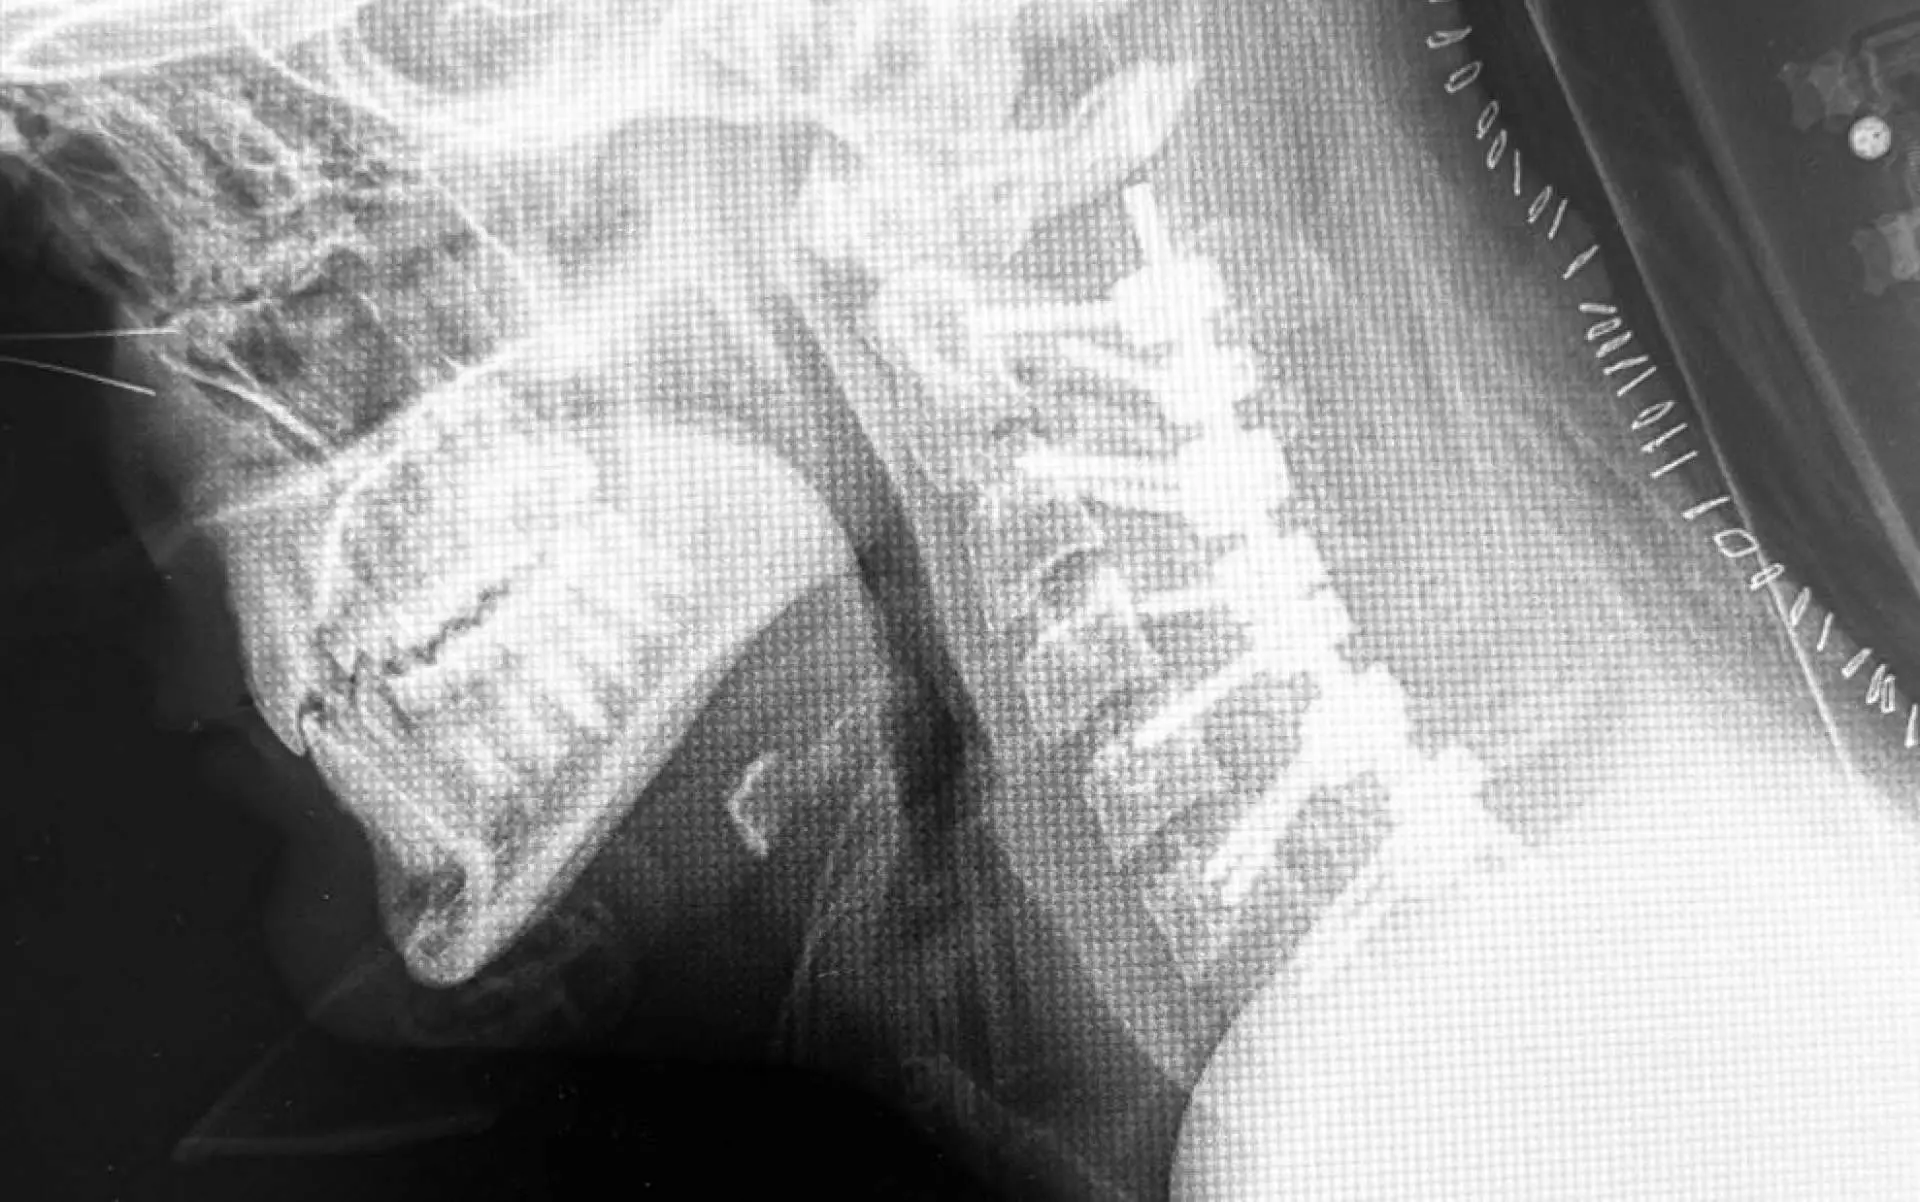

La cifosis post-laminectomía cervical es una curvatura anormal hacia adelante de la columna cervical (cuello) que puede ocurrir después de una laminectomía, que es un tipo de cirugía de columna. Esta condición puede resultar de la eliminación de parte de la lámina, que es una estructura ósea que cubre y protege la médula espinal, lo que puede alterar la estabilidad y la alineación de la columna vertebral. La gravedad de la cifosis y los síntomas asociados pueden variar y, en consecuencia, las estrategias de tratamiento también

Fusión Espinal: Unir dos o más vértebras utilizando injertos óseos y/o dispositivos de fijación como tornillos y barras para estabilizar y corregir la alineación de la columna vertebral.